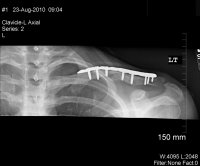

X-Rays:

Xrays

Update: August 23, 2010

Saw the Doc again, he's pleased with the results, but it's just going to take more time. If you look at the x-rays you can see that the void is closing, slowly.

He seemed very confidant that it should be ok by T-Day, will know more in 6 weeks.